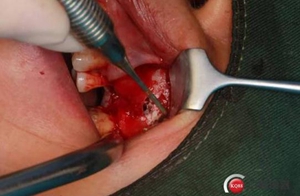

改良式外提升工具盒-外提 科貿(mào)嘉友收錄

大家好,我是梁老師的助理小依。由于梁老師每天手術(shù)檔期安排較滿,加上經(jīng)常出差講課,沒有時(shí)間整理病例 。為了方便大家更及時(shí)的了解梁老師最新手術(shù)動(dòng)態(tài),以后將由我為大家整理并推送梁老師最新經(jīng)典案例。案例文字旁白少,但圖片會(huì)盡量完整展示手術(shù)全過程,供大家學(xué)習(xí)參考。有任何問題,可以留言,梁老師會(huì)親自為大家解答。感謝大家對梁老師的支持和關(guān)注!